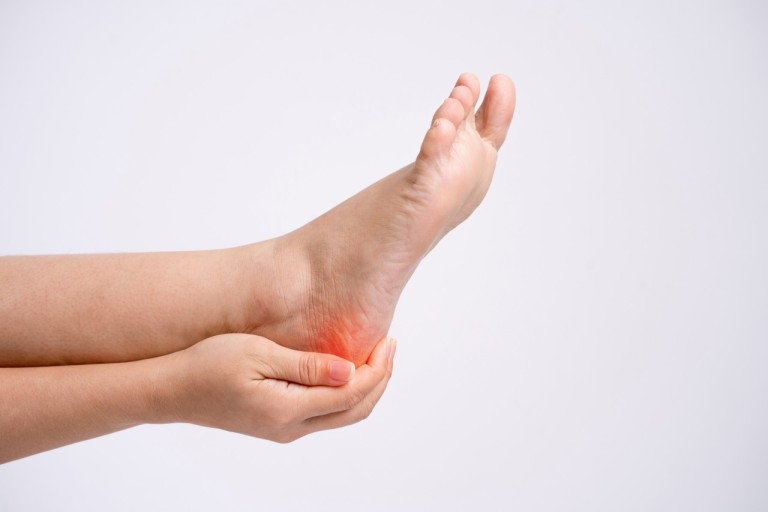

초기에는 밤에만 불편함을 느끼다가 점점 지속 시간도 늘어납니다.3. 족저근막염

발바닥 통증의 대표 질환으로,

발뒤꿈치에서 발바닥 전체로 이어지는 근막에 염증이 생기며

걷거나 서 있을 때 발바닥이 뜨겁고 찌릿한 통증을 유발합니다.

특히 아침에 첫 발을 디딜 때 더 아픈 경우가 많아요.